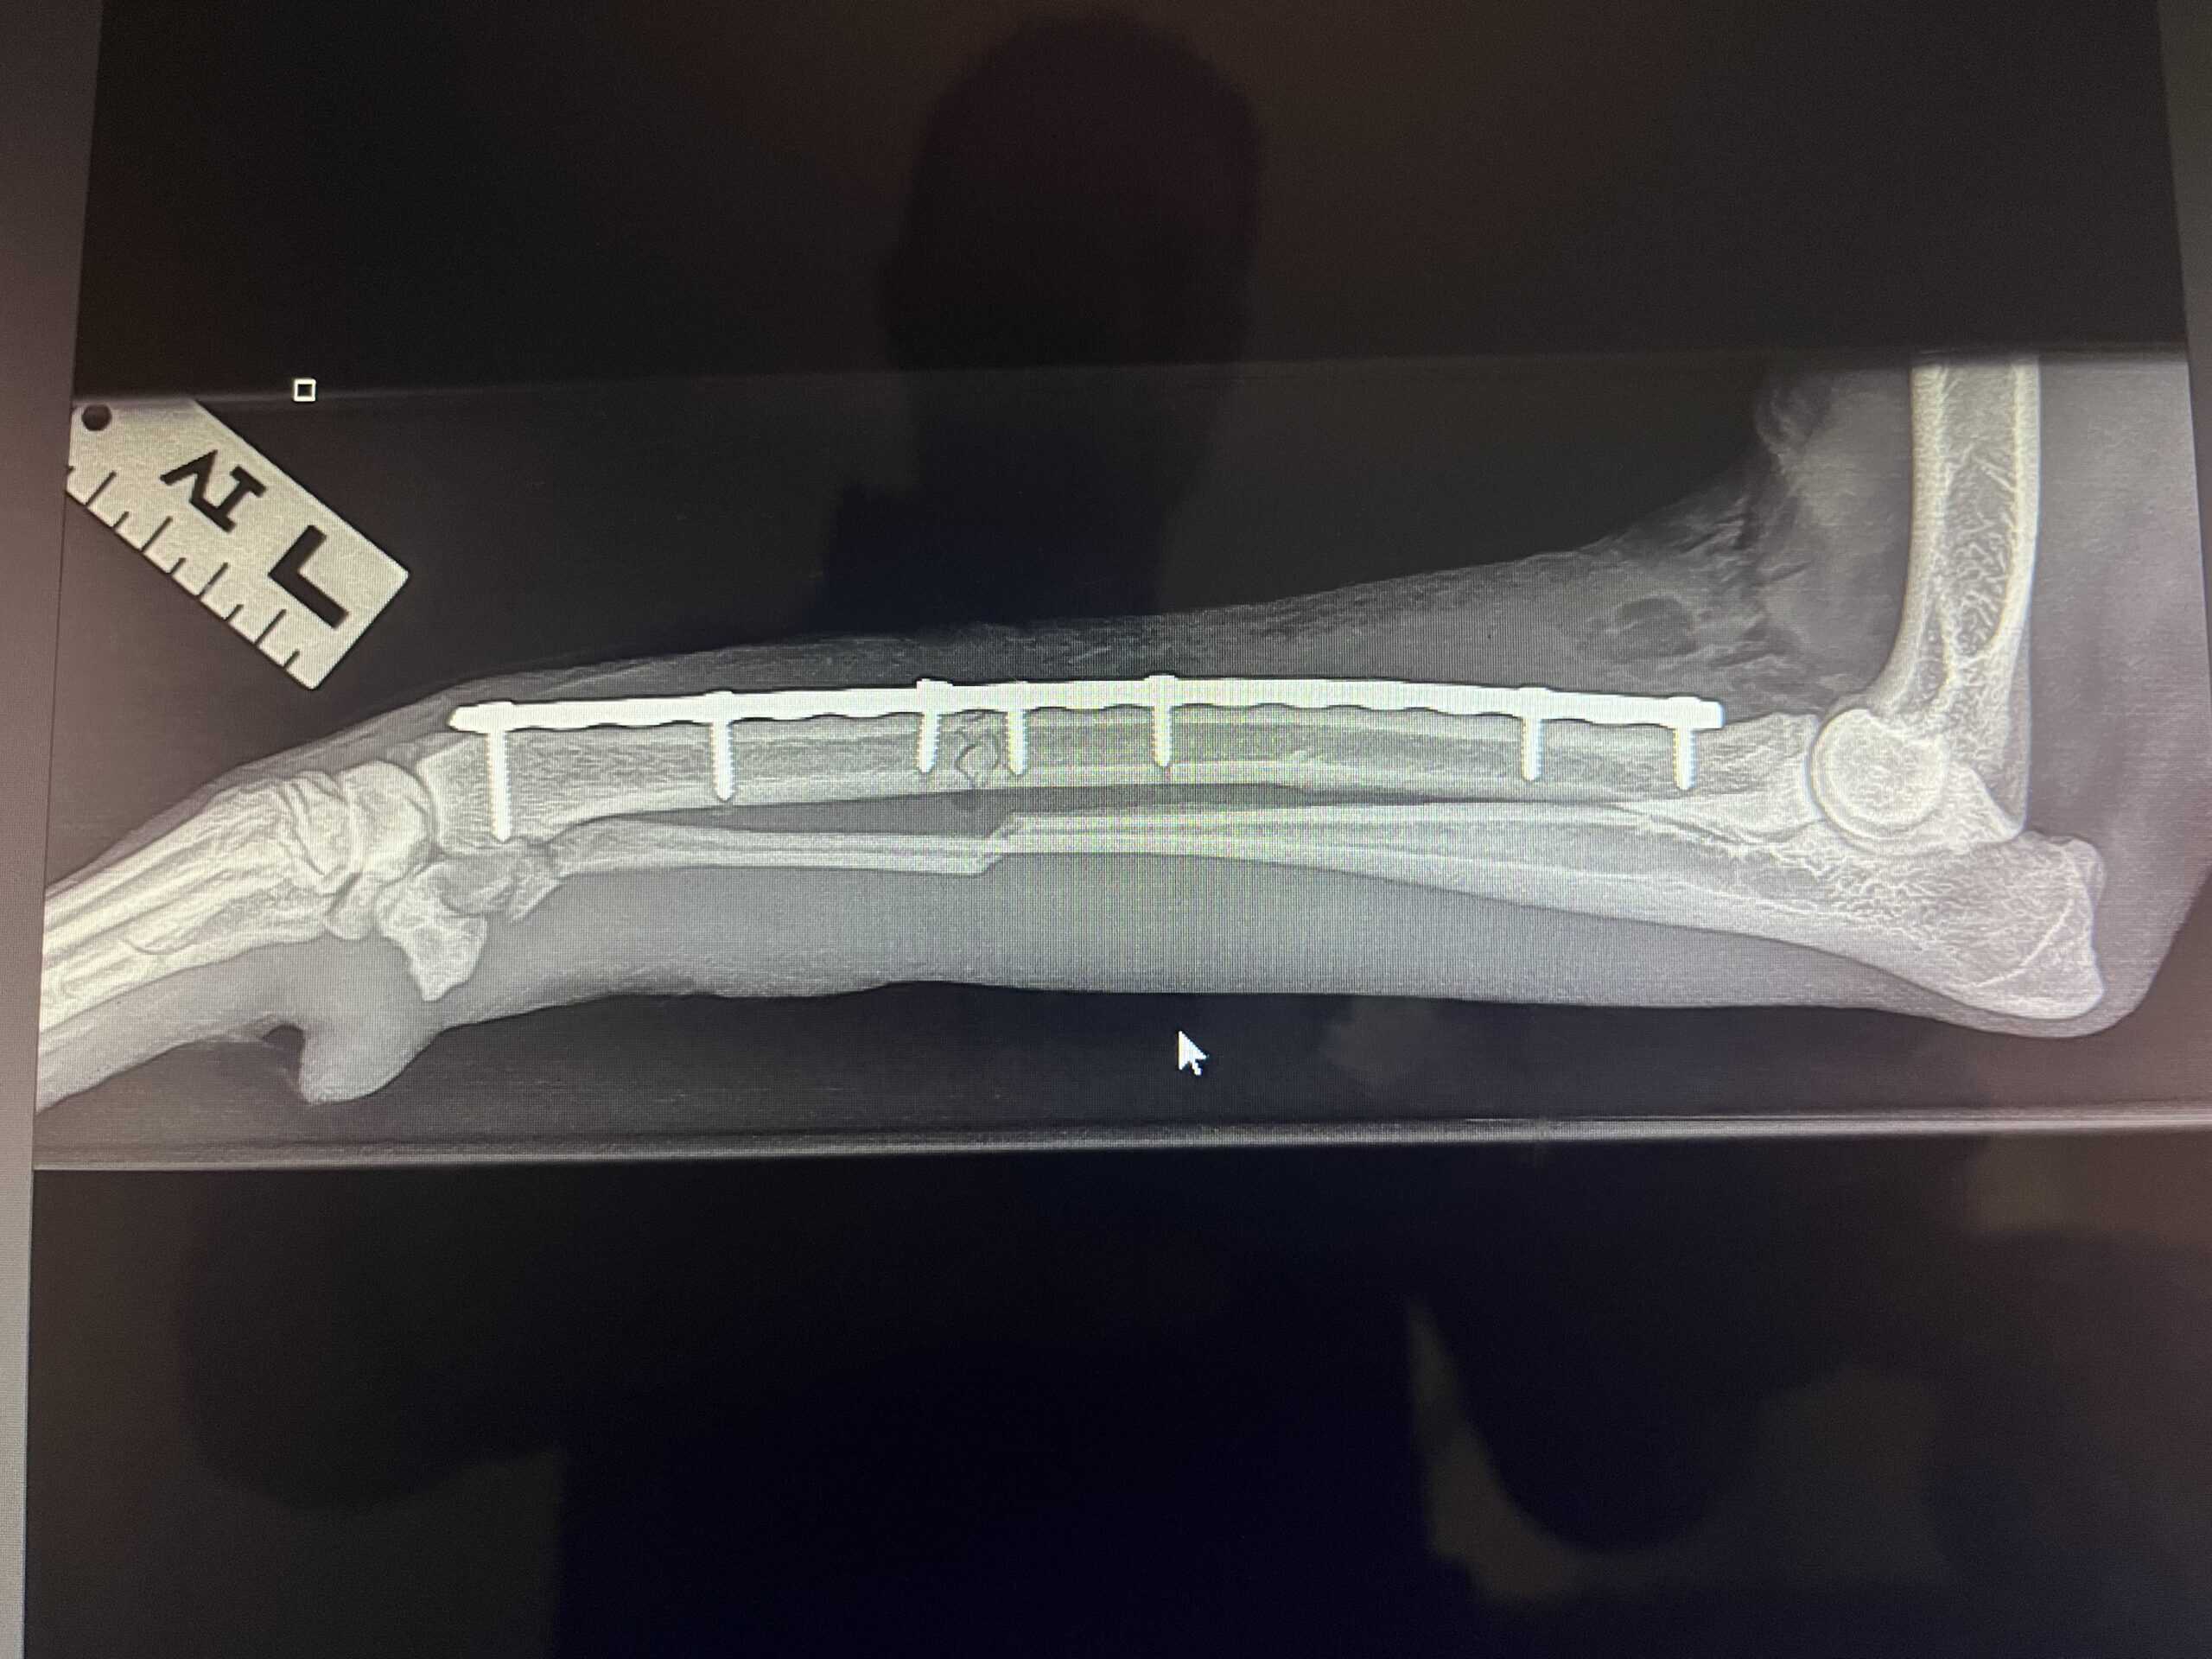

X-rays: Helpful in diagnosing fractures, joint dysplasia, tumors, and arthritis.

The most common imaging modality used to assess bone structure and joint integrity.

Fracture Diagnosis: Identifying the type, location, and severity of fractures.

Post-Surgical Assessment: Monitoring healing after orthopedic surgeries.

Fluoroscopy allows surgeons to visualize fracture alignment and hardware placement during orthopedic surgeries, such as the installation of plates or screws.